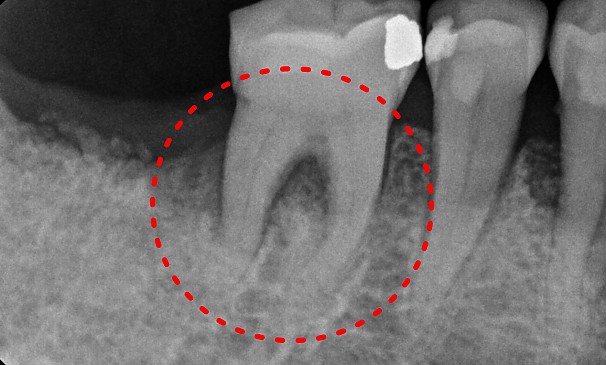

박OO님 전후사진 | 치료 기간 : 2주

치료 전

치료 후